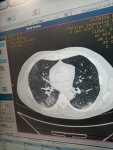

Я рентгенлаборант и 80% работы было связано с ковидными.Если есть вопросы задавайте...

Ниже мой КТ и то как вирусная пневмония SARS - Cov 2 выглядит на снимках кт